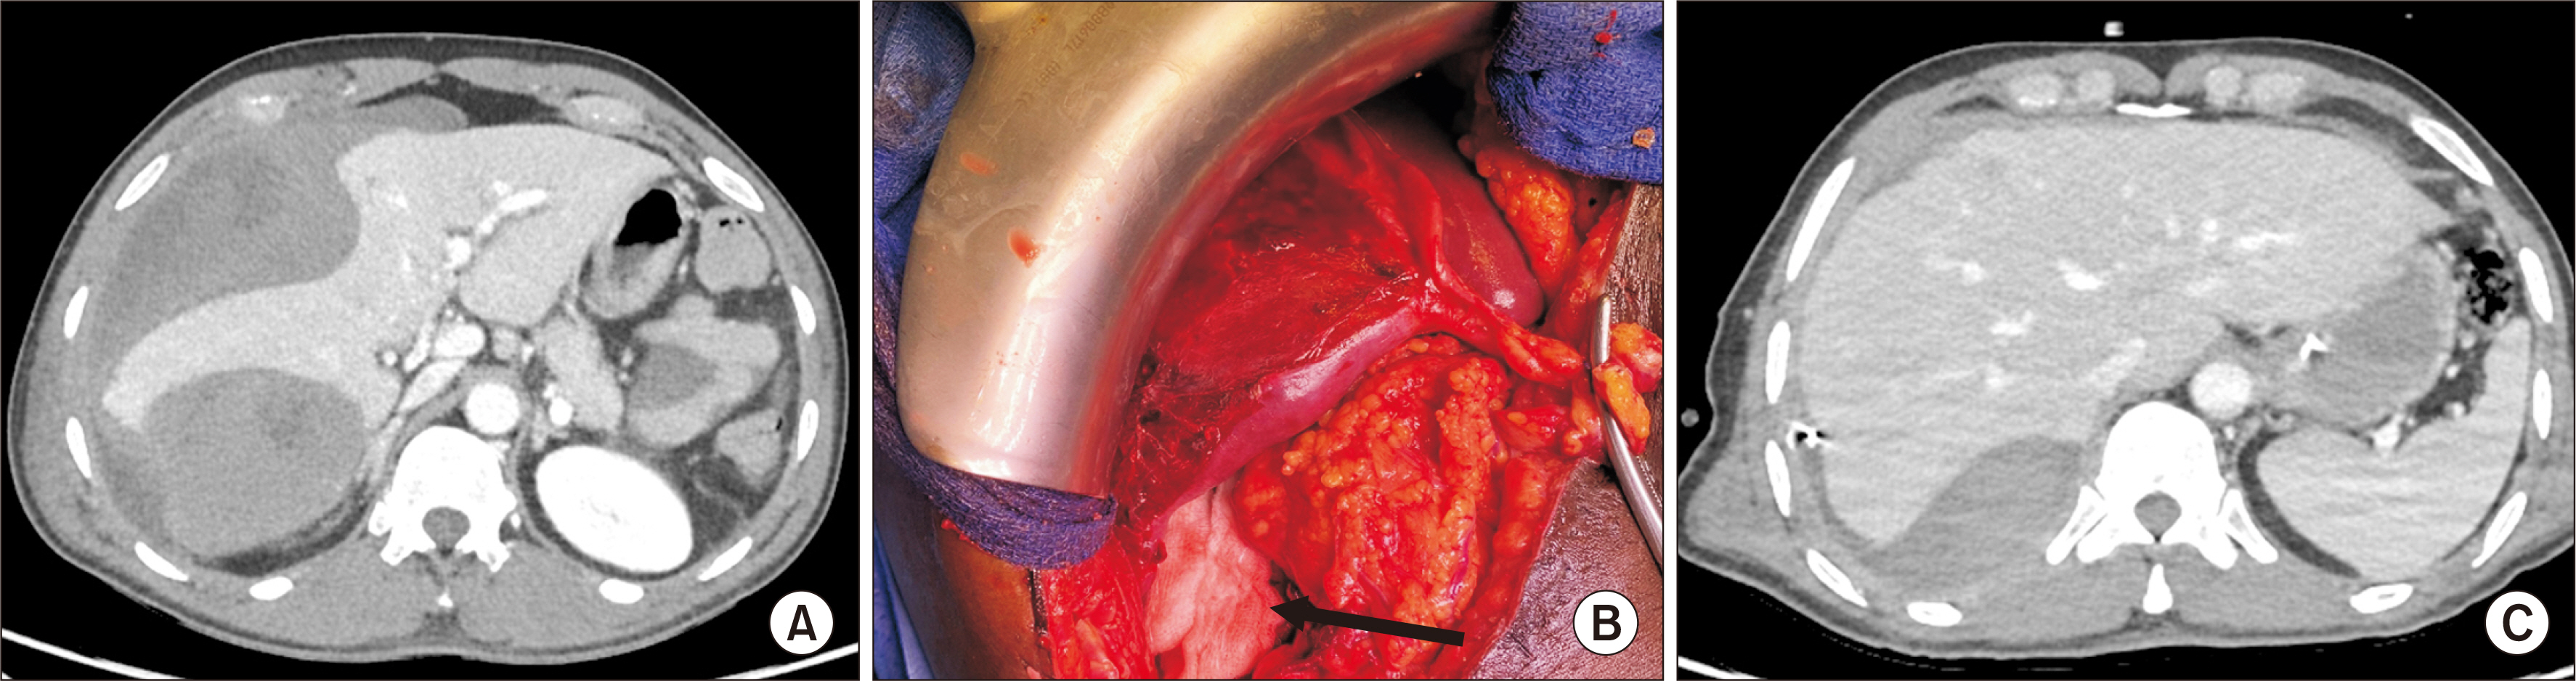

- Hepatic compartment syndrome (HCS) is a rare but life-threatening entity that consists of a decreased portal flow due to intraparenchymal hypertension secondary to subcapsular liver hematoma. Lethal liver failure can be observed. We report three cases, and review the literature. A 54-year-old male was admitted for extensive hepatic subcapsular hematoma after blunt abdominal trauma. Initially, he underwent embolization of the hepatic artery’s right branch, after which he presented clinical deterioration, major cytolysis (310 times the upper limit of normal [ULN]), and liver failure with a prothrombin time (PT) at 31.0%. A 56-year-old male underwent liver transplantation for acute alcoholic hepatitis. On postoperative day 2, he presented a hemorrhagic shock associated with deterioration of liver function (cytolysis 21 ULN, PT 39.0%) due to extensive hepatic subcapsular hematoma. A 59-year-old male presented a hepatic subcapsular hematoma five days after a cholecystectomy, revealed by abdominal pain with liver dysfunction (cytolysis 10 ULN, PT 63.0%). All patients ultimately underwent urgent surgery for liver capsule excision, hematoma evacuation, and liver packing, if needed. The international literature was screened for this entity. These three patients’ outcomes were favorable, and all were alive at postoperative day 90. The literature review found 15 reported cases. HCS can occur after any direct or indirect liver trauma. Surgical decompression is the main treatment, and there is probably no place for arterial embolization, which may increase the risk of liver necrosis. A 13.3% mortality rate is reported. HCS is a rare complication of subcapsular liver hematoma that compresses the liver parenchyma, and leads to liver failure. Urgent surgical decompression is needed.